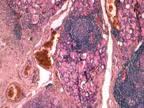

Biopsja tarczycy

Biopsja tarczycy odgrywa kluczową rolę w diagnostyce schorzeń tego narządu.

Komórki te są następnie oceniane przez specjalistów patomorfologów.